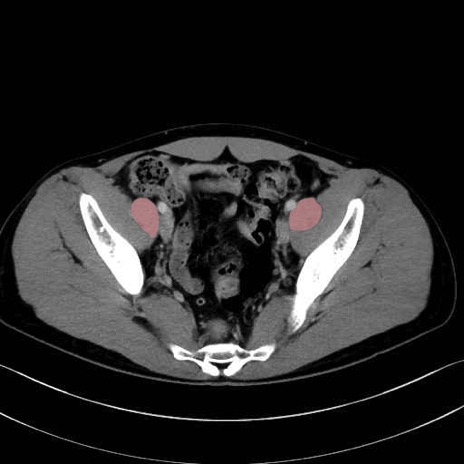

2. 腸腰筋群と骨盤底筋

大腰筋 (Psoas major)

腸骨筋 (Iliacus)

肛門挙筋 (Levator ani)